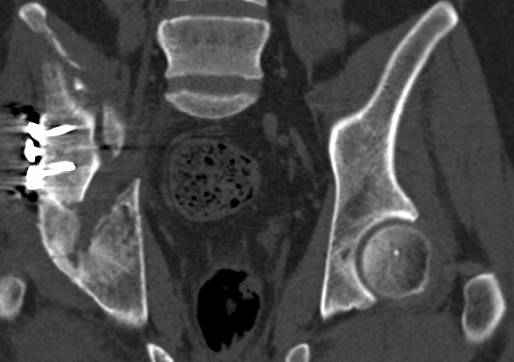

Интересно было бы посмотреть рентгенограммы до операции. У меня впечатление, что я не все вижу, что тут есть... Уважаемые Господа "тазисты" и "тазологи", к какому типу переломов вертлужной впадины по Летурнелю вы бы отнесли это случай?

Из переломов проходящих через крыло и/или заднюю стенку ни простой перелом "передней колонны" (явно имеется пером задней стенки, и не видно перелома седалищной или лонной), ни простой "поперечный", ни ассоциированный "Т-образный" (т.к есть перелом крыла и не видно перелома седалишной), ни ассоциированный "задняя колонна+задняя стенка", на ассоциированный "поперечный+задняя стенка", ни ассоциированный "передняя колонна+задняя гемисфера" (не видно перелома седалищной), ни ассоциированный "обе колонны" (не видно перелома лонной седалищной) не подходят под эту классификацию....

к таковым себя не причисляю, но...обычное дело для нашей страны - выкладывать 3D и не показывать стандартные проекции Judet. Дигност представляет те ракурсы, которые по-его мнению наиболее информативны, более того комп сам достраивает какие-то мелкие повреждения по 3D по своему усмотрению. По данной реконструкции можно предполагать высокий двухколонный перелом с оскольчатыми передней и задней колоннами, оскольчатую высокую переднюю колонну с задним полупоперечником или одно из перечисленных с вовлечение КПС. У меня впечатление за второй вариант, но нужно обследовать нормально - проекции, сканы.

высылаю дополнительно сканы.

итак, второй вариант: высокий двухколонный с вовлечением КПС... Ни одно из основных повреждений не репонировано, кроме задней стенки. Скорее всего попытка реконструкции вертлуги сейчас будет очень травматичной и не очень эфективной, т.е. вероятный риск более значим, чем ожидаемая польза... Лучше подождать, и потом сразу эндопротез

подождать сколько, чего? такая дыра в задней колонне не закроется никогда.

потом эндопротез какой? в такой ситуации приходит на ум Burch-Schneider cage, в 35 лет, дальше что делать?